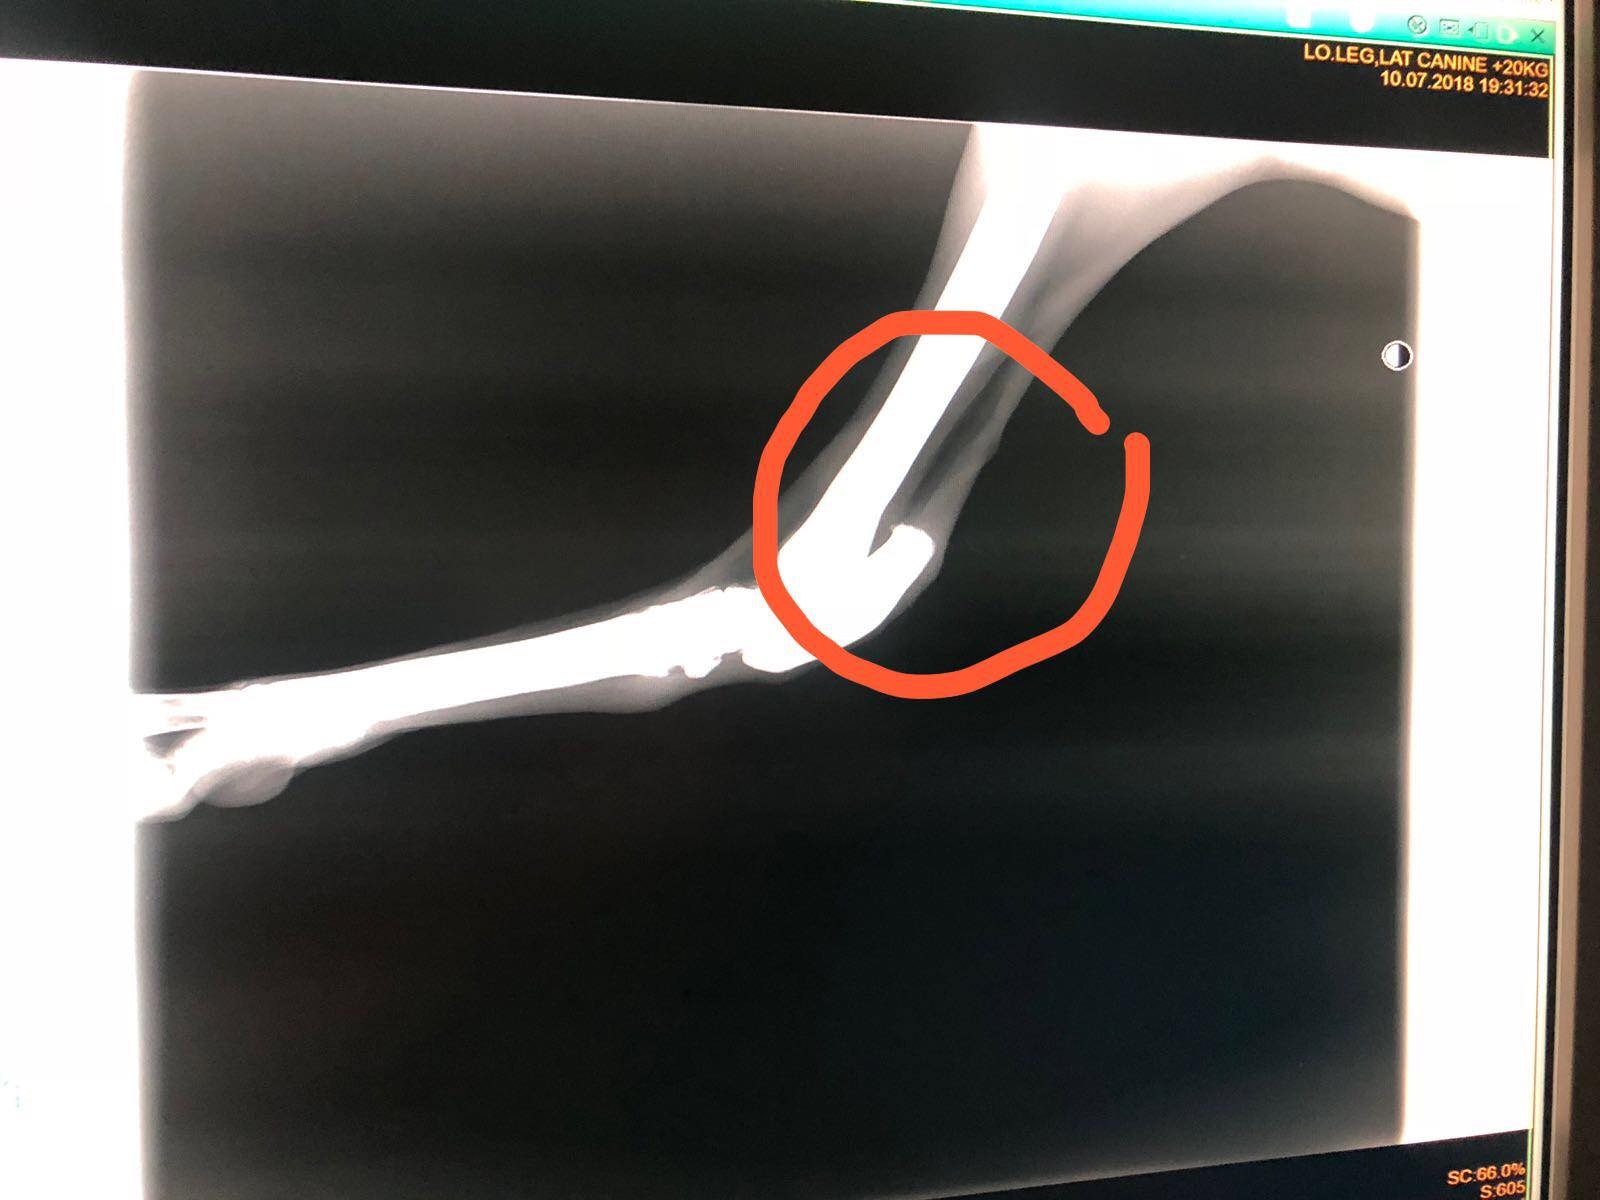

澳門愛護動物協會主席Albano Martins在星期二(7月10日)於社交媒體Facebook表示,成功拯救了一隻有腳傷的雄性格力犬Ko Ko,約6歲半。Albano Martins表示,Ko Ko本是被一名內地人領養的,後來將牠遺棄於澳門政府狗房,澳門愛協同日便到狗房接走Ko Ko。愛協其後帶Ko Ko到獸醫診所作檢查,Albano Martins上傳了幾張Ko Ko腳部的X光照片,指牠腳部受傷。

Ko Ko腳部的X光照片 (Albano Martins)